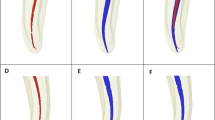

The cross-sectional design and stiffness of the instruments have been identified as factors potentially influencing preparation outcomes [27, 28]. Three different files (Pro-G, WOG-G, and TRN-G) for creating a glide path were examined in this study. Despite their small size, the tested instruments have different cross-sectional designs and tapers: a parallelogram with progressively tapering (of WOG-G), a square with progressively tapering (of Pro-G), and an off-centered parallelogram with variable tapering (TRN-G). These features effectively increase flexibility and adaptation to the curved canal anatomy [12, 29]. TRN-G, Pro-G, and WOG-G have similar nominal sizes and tapers. Since these various features cannot be fully isolated, this could be considered a limitation in the unambiguous interpretation of the results [30].